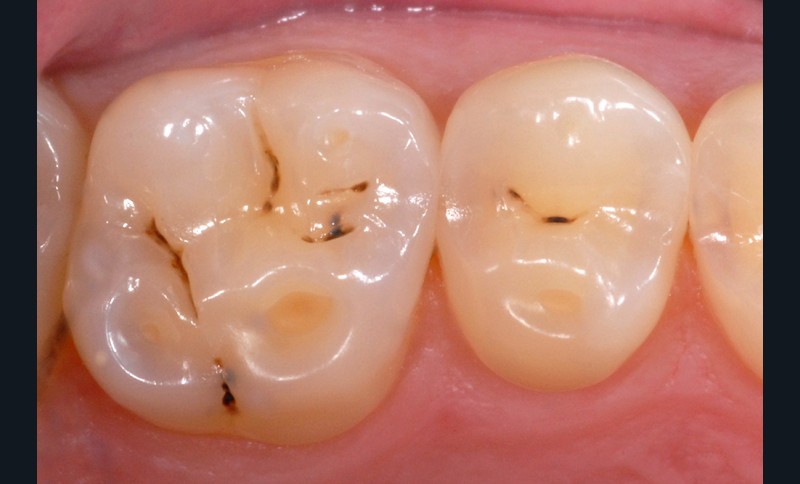

Elle correspond au déplacement de deux corps solides l’un contre l’autre avec interposition de particules abrasives qui constituent le troisième corps. Lorsqu’elle est généralisée à l’ensemble de la denture, elle est essentiellement liée à la charge abrasive du bol alimentaire qui affecte physiologiquement l’ensemble des faces dentaires lors de la mastication. Les surfaces d’usure sont émoussées, satinées, brossées, avec des limites de contour arrondies.

Lorsque l’abrasion est focalisée, en général au niveau cervico-vestibulaire, elle est essentiellement liée au brossage dentaire. Les particules abrasives contenues dans le dentifrice constituent le troisième corps qui s’interpose entre la brosse et les dents. Dans certains cas pathologiques favorisés par un environnement acide, la dentine radiculaire plus ou moins dénudée s’abrase fortement en cas de brossage iatrogène. D’importantes lésions cervicales non carieuses peuvent alors apparaître en peu de temps (fig. 3).